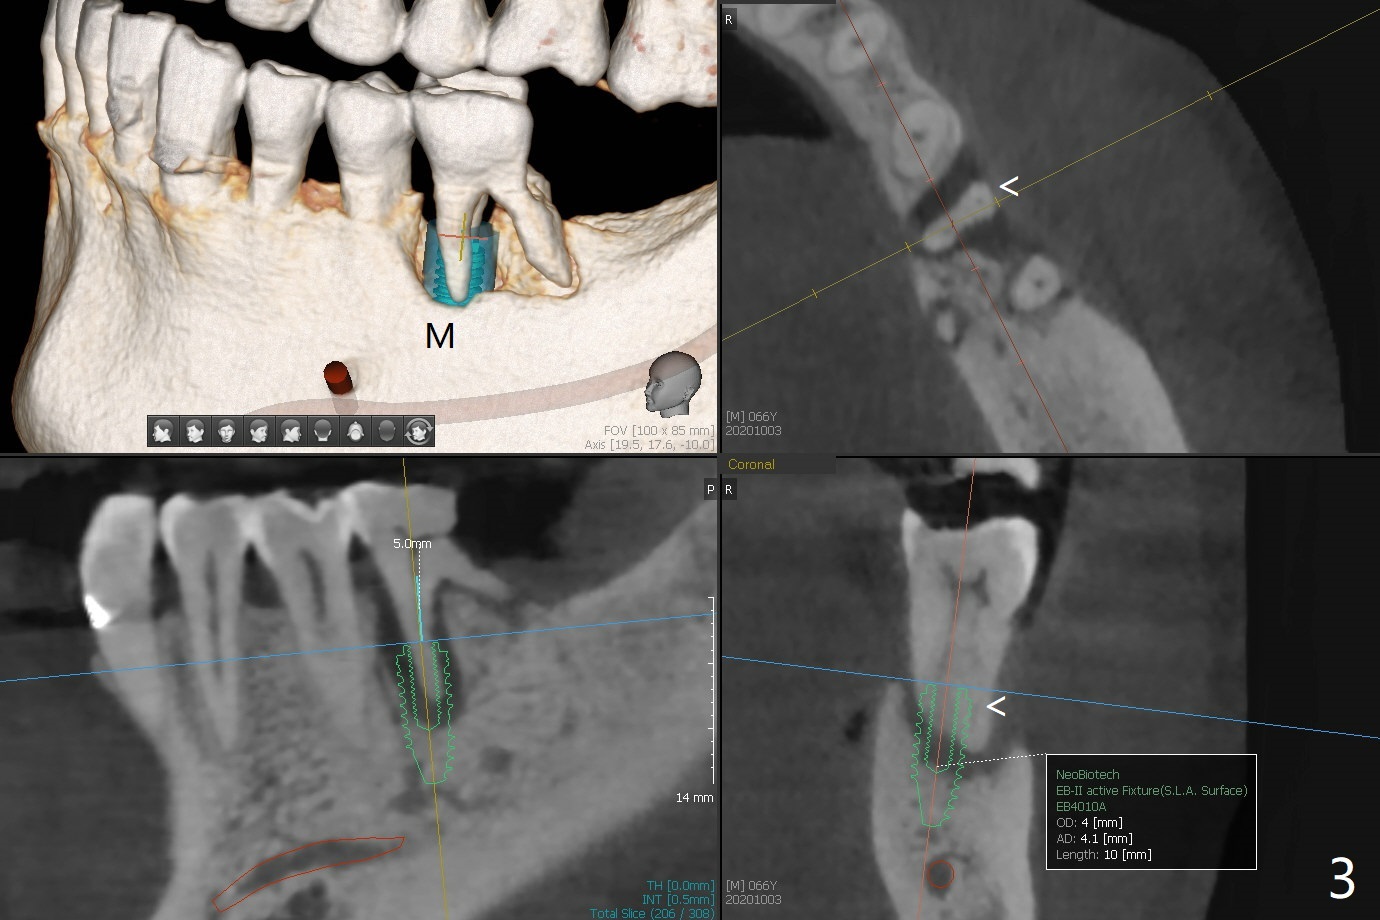

66岁男要求拔除左下6(图一),中隔好像斜型吸收(S),如果即刻植牙植入中隔,冠方螺纹三面暴露(图二:箭头)。当植入近中牙槽窝(图三:M),似乎只有一面螺纹暴露。病人右下3,4颊侧骨板仿佛植骨后修复,不妨尝试同样方法。不过需要如下改善:尽量少制备粘性骨块,用剩余PRF上清液临时调袢骨粉,放置牙槽窝底部(好压紧),而粘性骨块放在颊侧缺陷和牙槽窝开口(防止下面骨粉脱落),最后放置PRF膜。安置间隙维持器,拍摄根尖片,放置牙周敷料(避免缝线)。